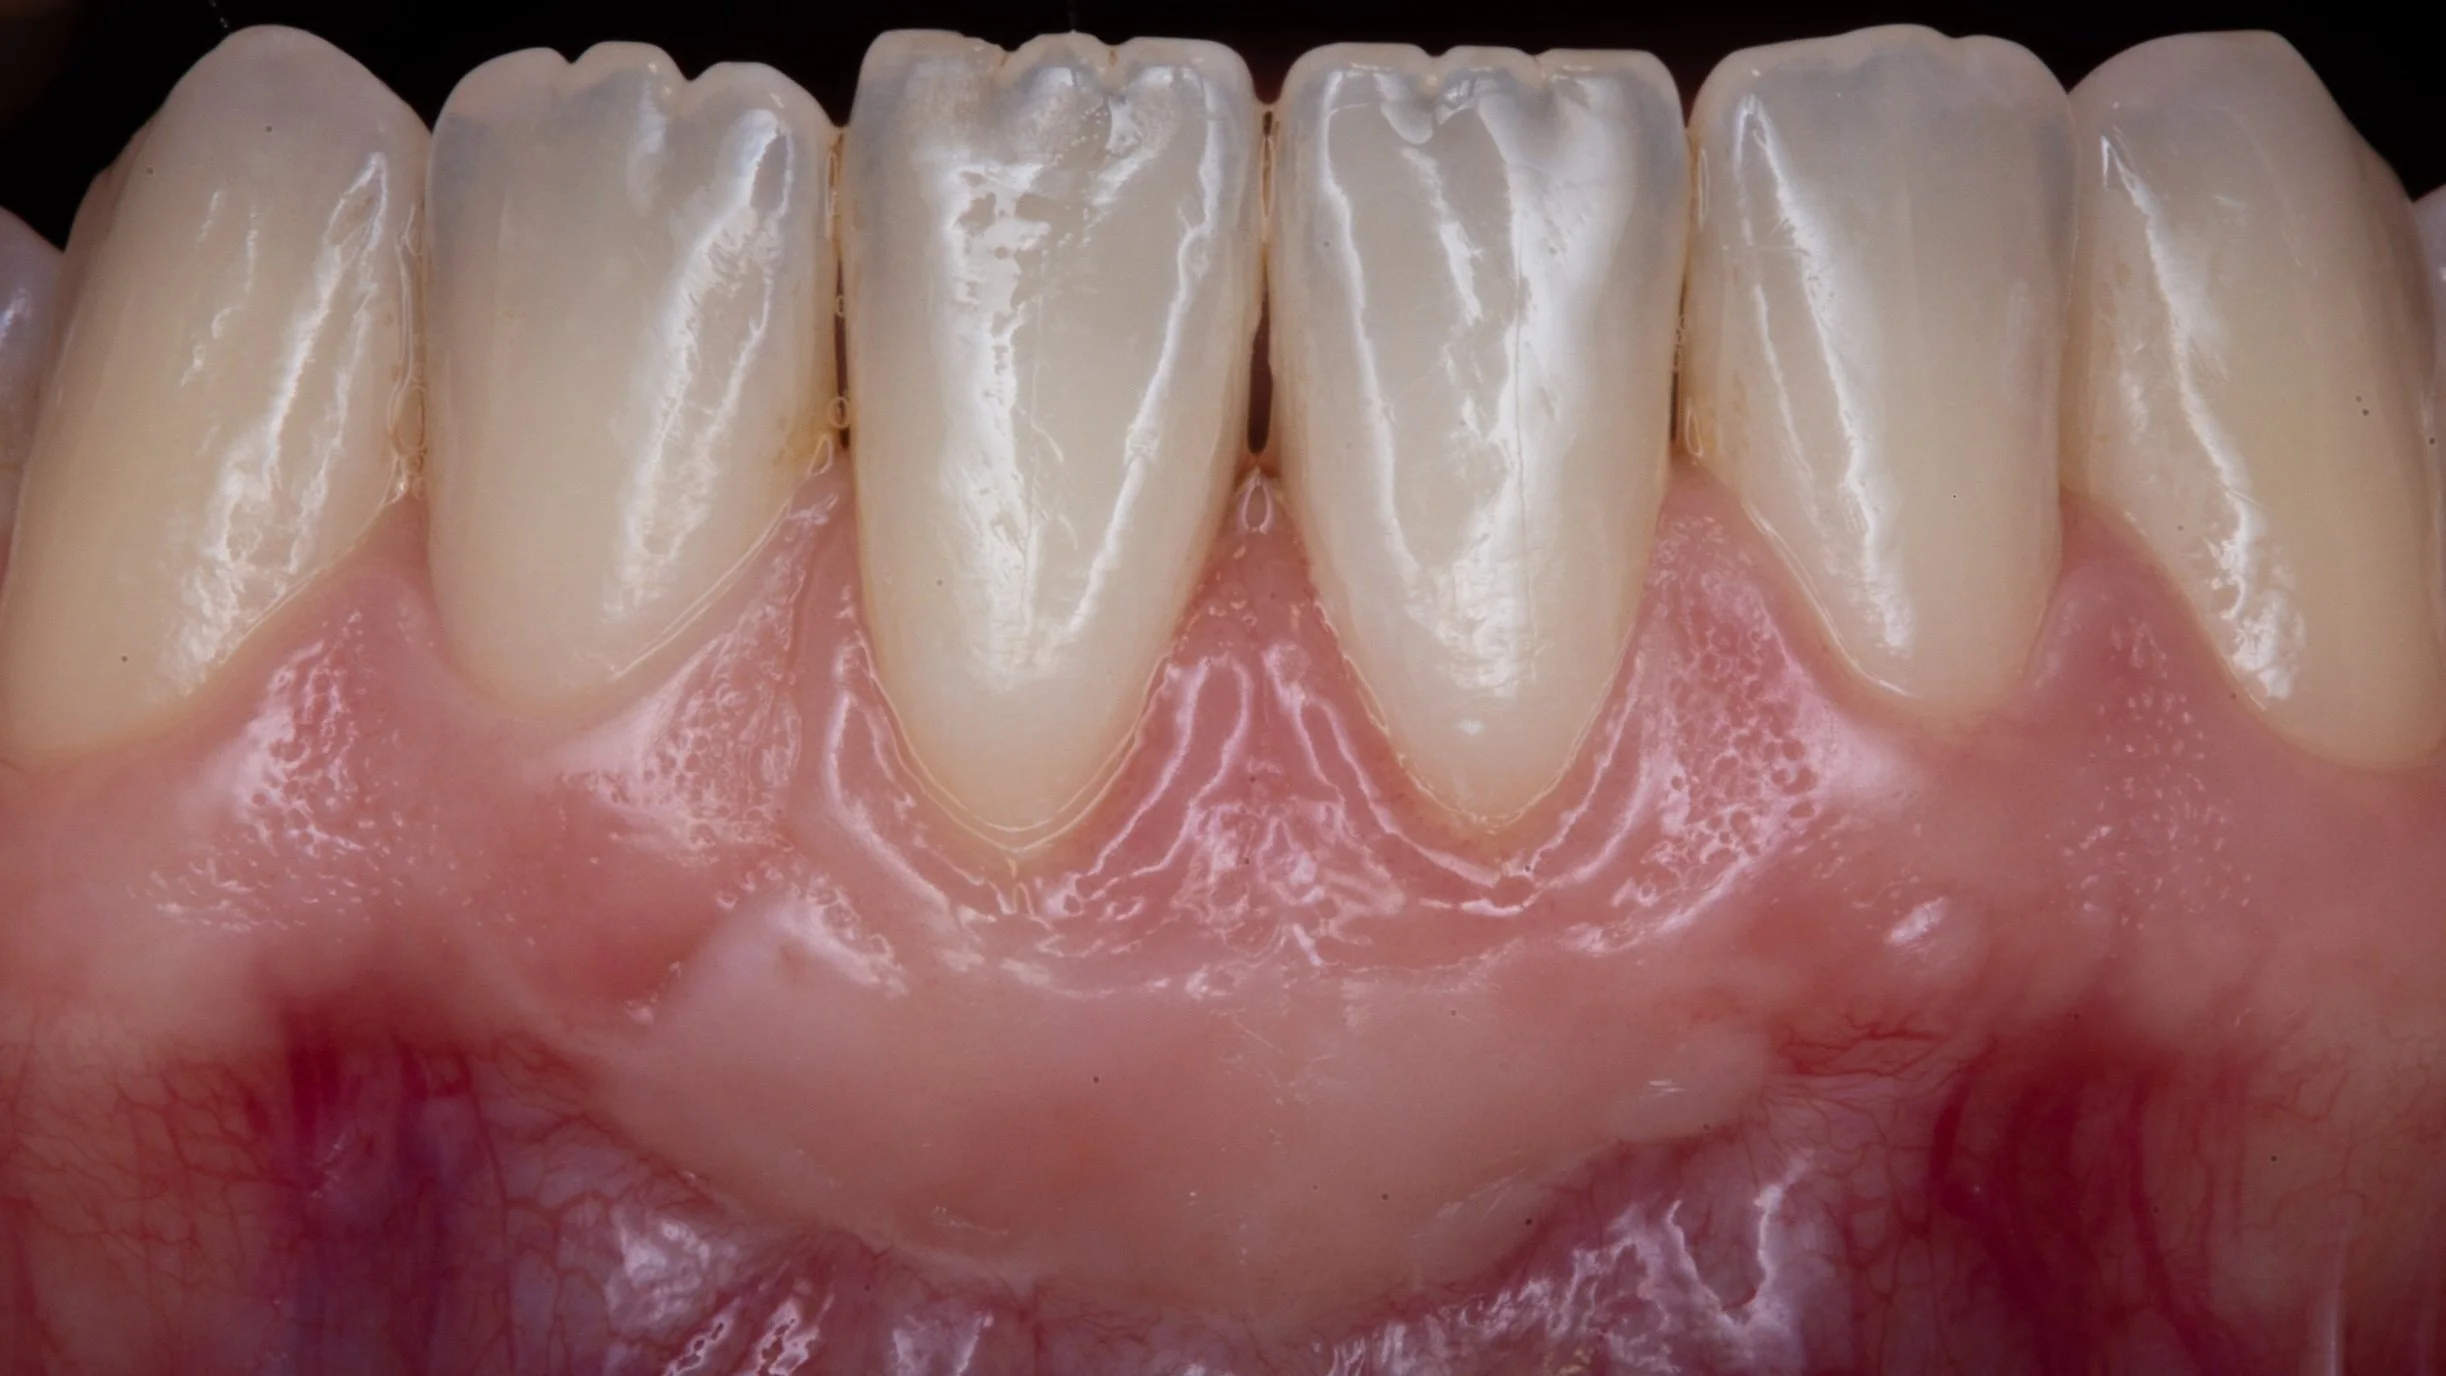

Gum recession is a common dental condition that you may have been referred to a periodontist to evaluate. If you have gum recession, the pink gum tissue surrounding teeth has pulled away from your tooth, exposing more of the tooth or its root. As shown in the before and after pictures on this page, gum recession can occur anywhere in your mouth, and may require surgical intervention. Gum recession can occur due to several reasons, including: